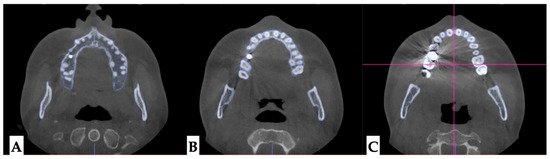

2.3.1. Surgical Protocol

2.3.2. Design of 3D Surgical Guide